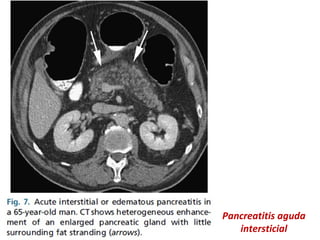

PANCREATITIS INTERSTICIAL EDEMATOSA

Edema intersticial, con realce homogéneo o ligeramente

heterogéneo del parénquima.